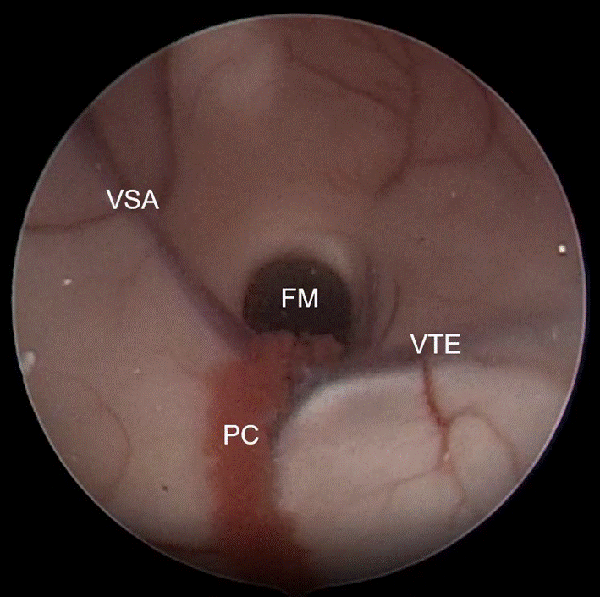

En los quistes intraventriculares o de línea media se ingresó al ventrículo lateral derecho y se realizó un reconocimiento anatómico, a fin de identificar el plexo coroideo y el foramen de Monro (Figura 2).

Figura 2: Imagen intraoperatoria del ventrículo lateral derecho en el cual se observa los tres principales reparos anatómicos que se dirigen al foramen de Monro (FM). PC: plexo coroideo, VSA: vena septal anterior, VTE: vena tálamo-estriada.